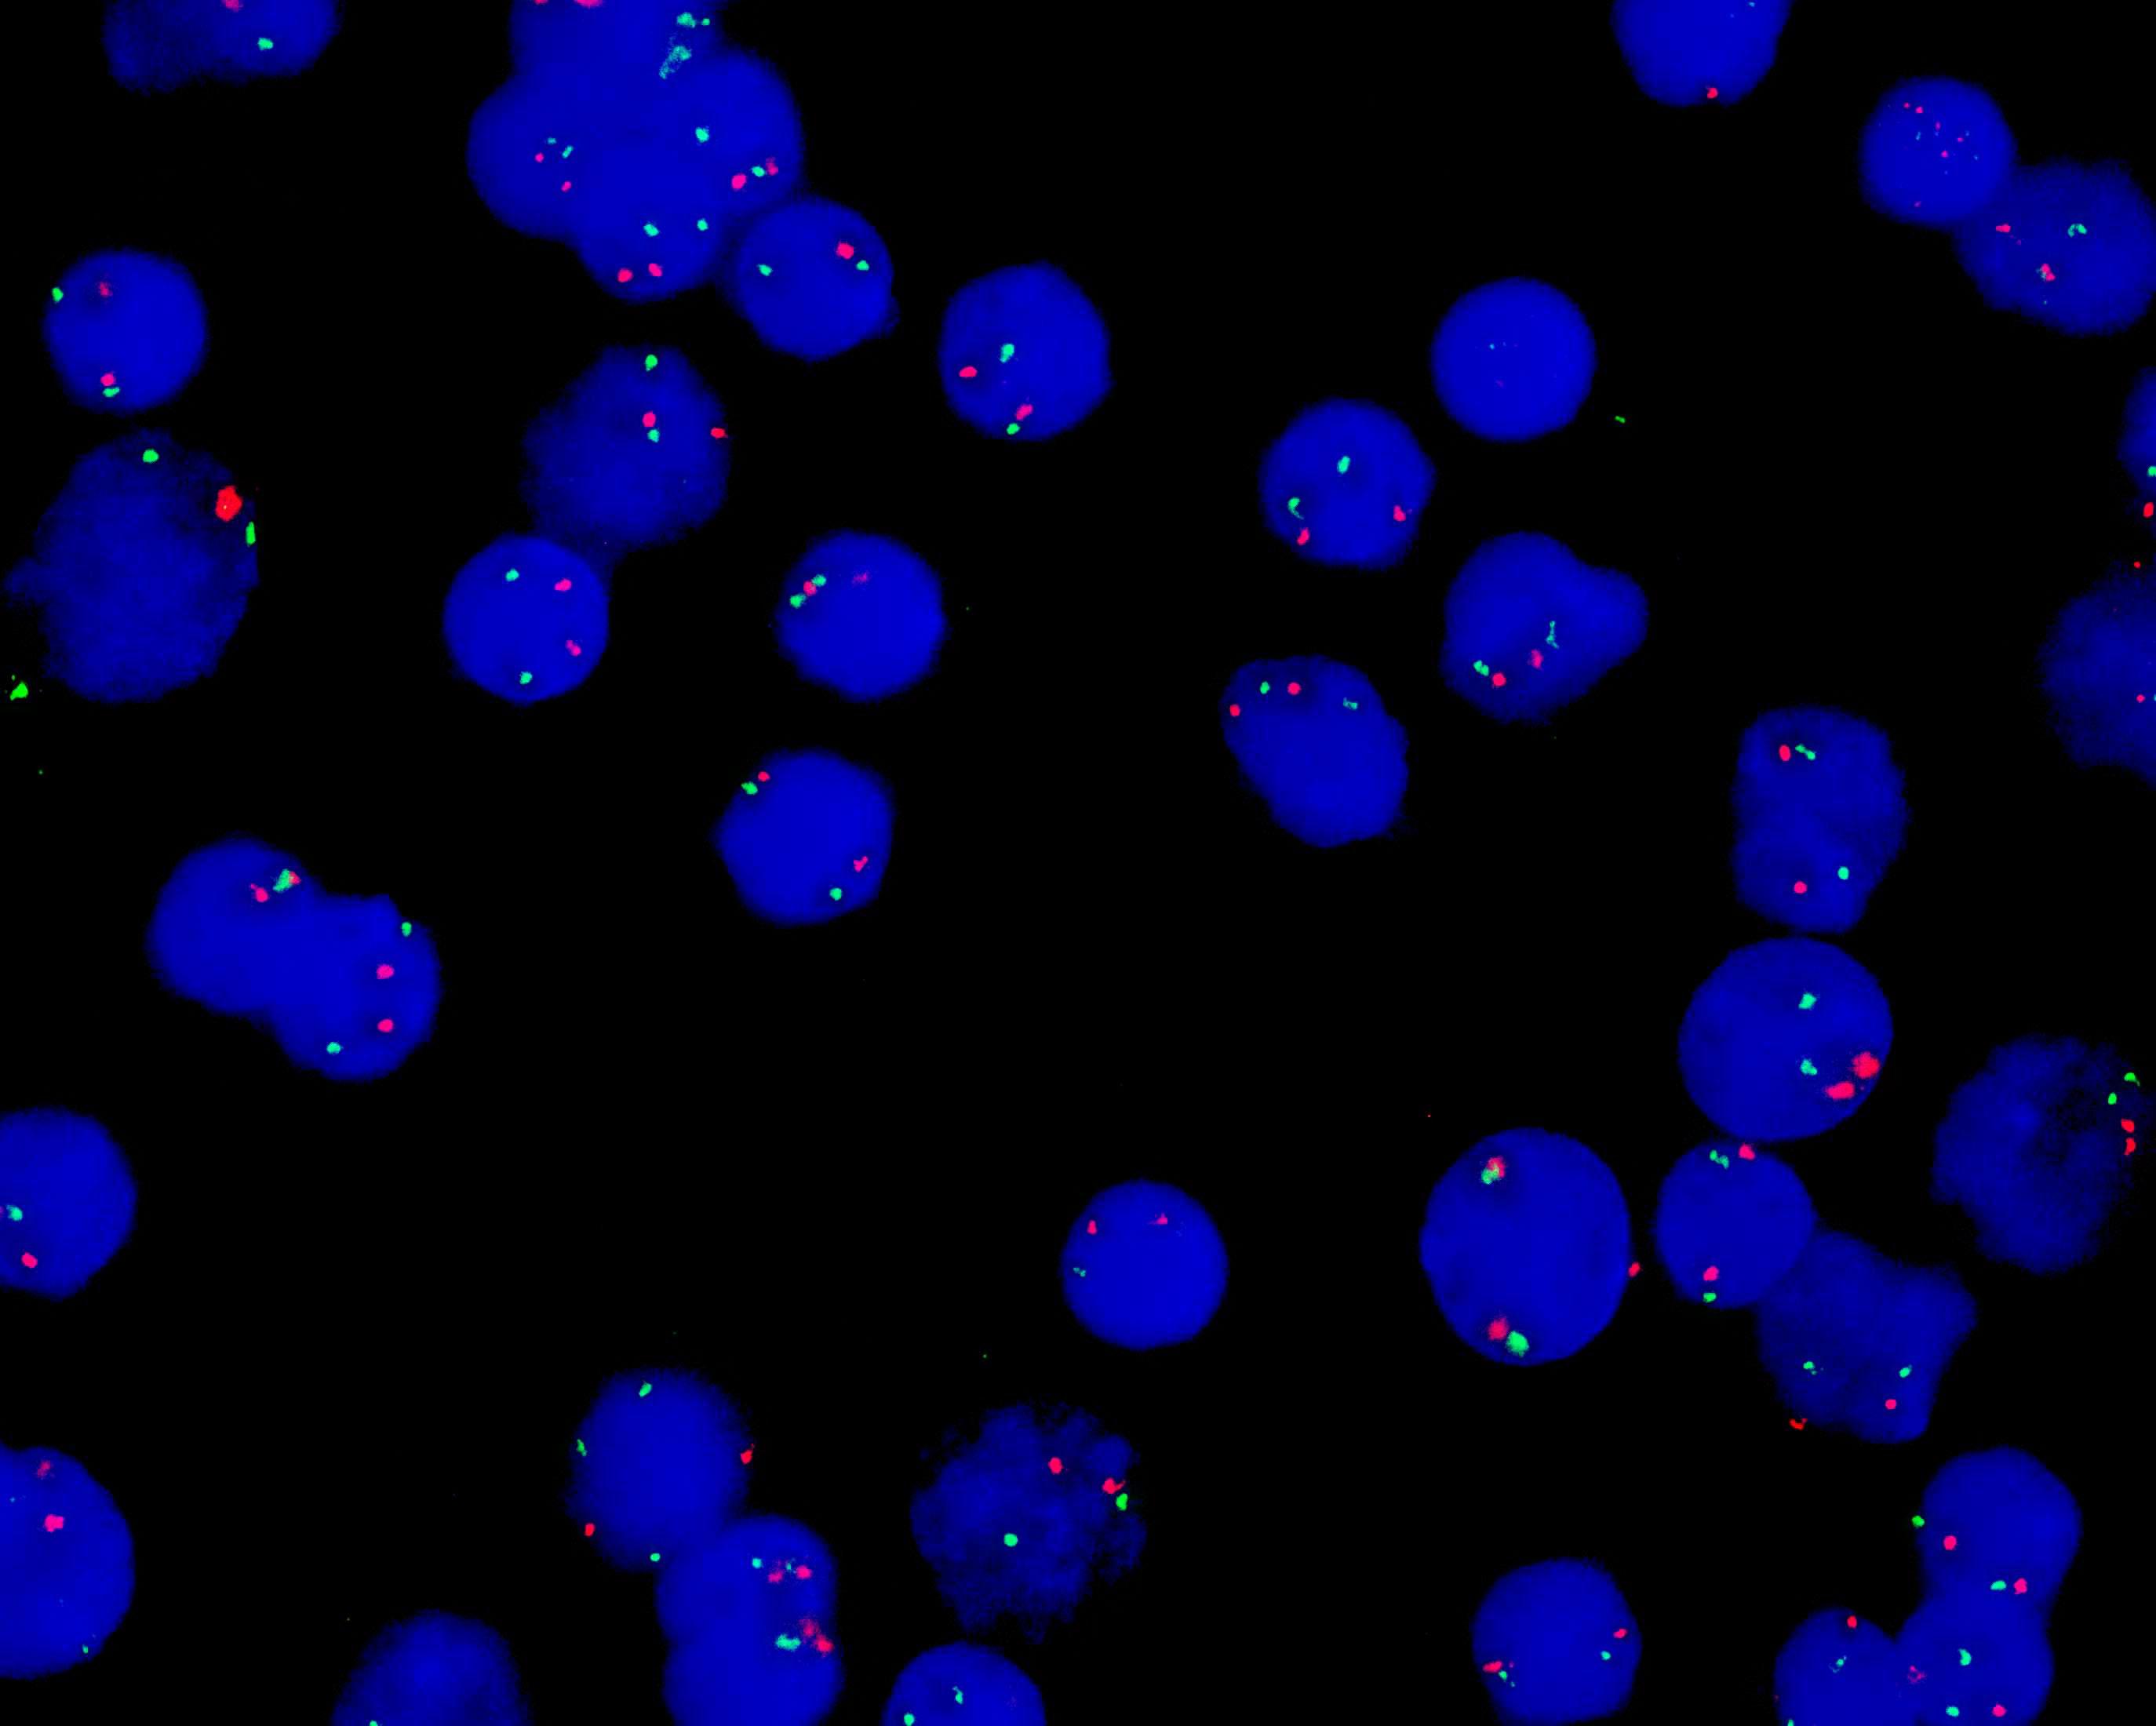

CSF1R/D5S630 dual color probe

CSF1R gene (5q32) labeled as orange, with a length of 360 kb; D5S630 locus labeled as green, with a length of 540 kb.